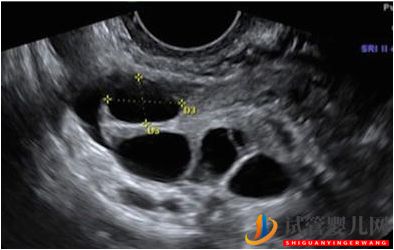

這是一個典型的超聲檢查,顯示一個卵巢有4個卵泡(中間的黑眼圈),每個都含有一個卵子。